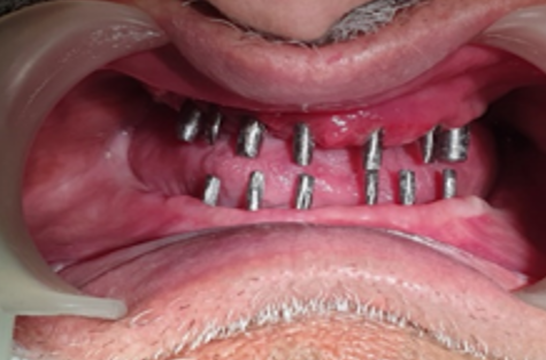

Implant-Retained Overdentures Implant Attachments, underside of dentures showing over denture Attachments:  Ball attachments, help to snap a denture into place – Enhanced Stability

Implant-supported Denture is securely anchored to the jawbone with dental implants, offering enhanced stability compared to traditional dentures that rest on the gums.

Enhanced Stability: Only 2 to 4 implants are typically needed to stabilize a full denture (12-14 teeth), providing a secure fit with significant cost reduction compared to full-mouth fixed _Implants.

Dentures anchored by implants for improved stability in elderly patients